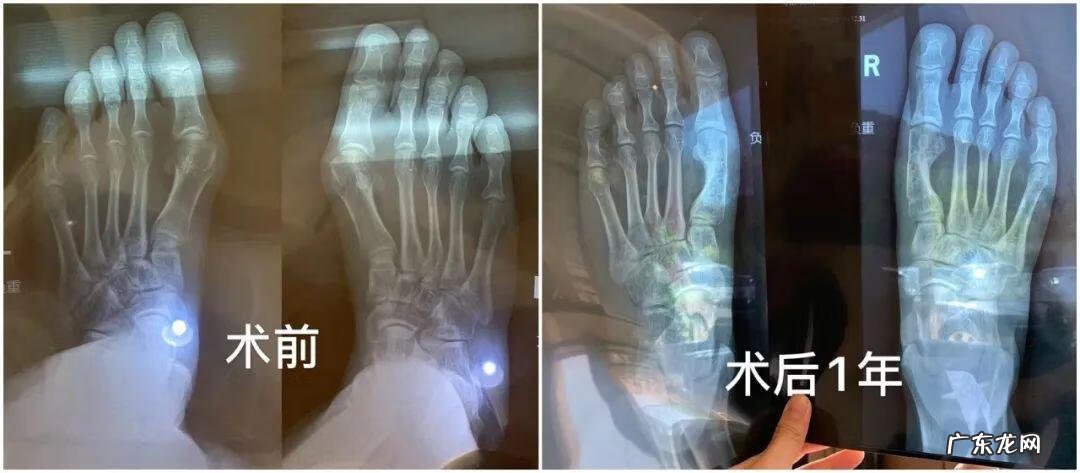

还有每次写高跟鞋都会有人烦恼的问题——拇指外翻 。也有小伙伴去做了修复手术,来看看她的分享:

其实拇外翻是一种疾病,所以算是治疗手术,它是可以医保报销的!不算美容!

很多人以为拇外翻只是脚丑,我去年疼痛剧烈,甚至无法走路,立刻在网上找到一位非常合适的三甲医生立刻就做了 。传统方式,断骨重接,并不是单纯切掉歪出来的那一块然后掰脚趾头!拇外翻一定不能做微创!一定不能!谁做谁后悔!

住院三天,术后可以脚后跟点地去厕所,卧床到下地一个月,三个月可以恢复剧烈运动 。现在不疼不歪不丑,穿鞋美美的了!

医保前23000,医保后8700 。我选择了可吸收钉,强度不如钛钉但没有内固定物,几年以后就被人体吸收没了 。钛钉强度高,下地时间早,但总归是脚里有个钉子不是 。

皮肤疤痕恢复时间因人而异了,有人3个月就看不到了,有人几年还有增生,但疤痕相对拇外翻的问题来说都是小问题了,疤痕在侧面,基本看不到 。全部注意事项就是遵医嘱!